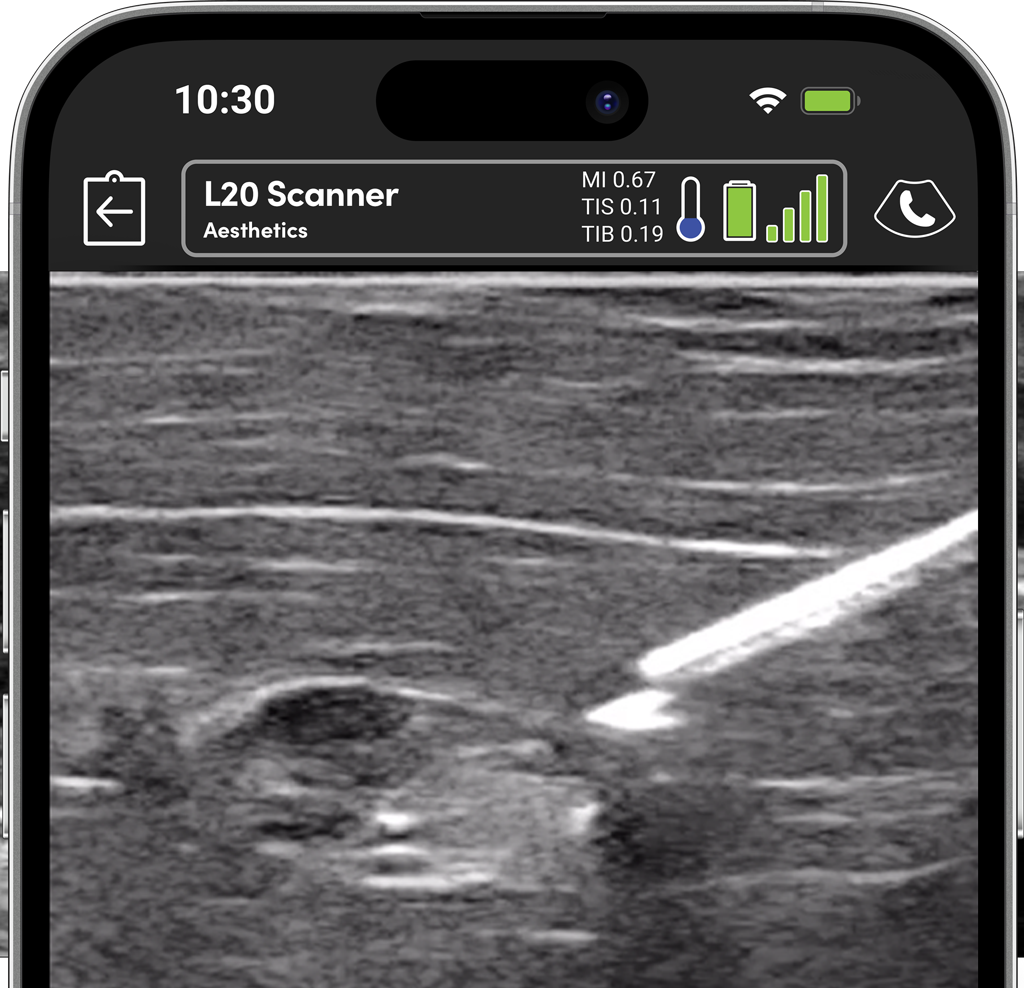

From dissolving fillers, vascular mapping, placing drains, to managing complications, ultrasound can support you at every step of the way.

Using ultrasound to guide filler placement reduces the risk of complications and helps to monitor the filler over time, allowing you to decide when to dissolve or refresh the filler. Color and power Doppler are essential tools for managing vascular complications.